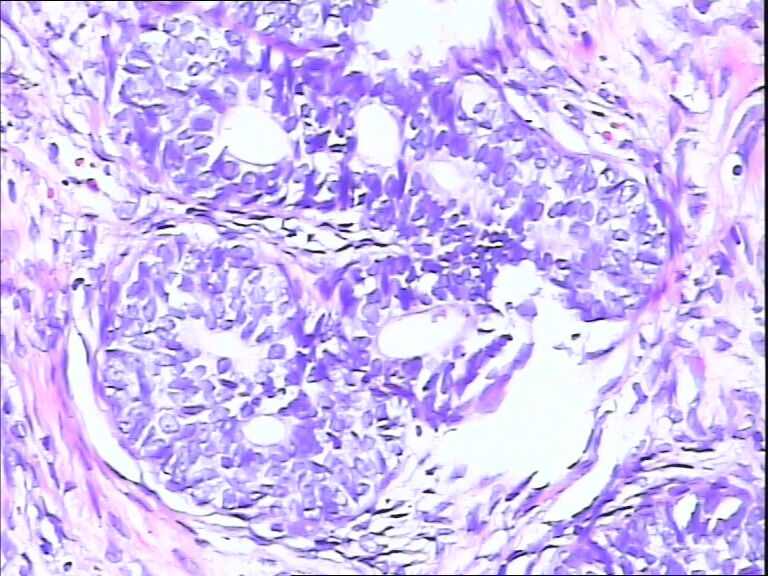

看不到核仁,PIN3。

筛状结构,可见小核仁,做一下标记:P63、34βE12,如果阴性,则是前列腺腺癌。

作P63、34βE12、P504S

良性增生。

基底细胞增生

结构复杂,核大但其染色欠佳,建意做免疫组化

感觉肌上皮细胞存在,良性增生?

考虑前列腺良性增生伴基底细胞增生,但细胞模糊,建议再切片染HE或IHC鉴别诊断。

考虑HGPIN

前列腺增生症,局部呈PIN改变,建议免疫组化进一步明确

基底细胞增生?HPIN?前列腺癌?

只有做标记了才放心。P63, 34BE12,P504S

前列腺腺样基底细胞肿瘤,可做:34βE12,CK5/6,P63,PSA,P504S标记进一步证实。

增生的都是基底细胞,可有核仁

筛状结构,可见小核仁,初步考虑PIN3,建议做免疫组化,34βE12,CK5/6,P63,PSA,P504S标记进一步证实。

片子切的不太好,有点厚,觉得恶性不能除外,不做免疫组化我是不敢发了

前列腺腺癌